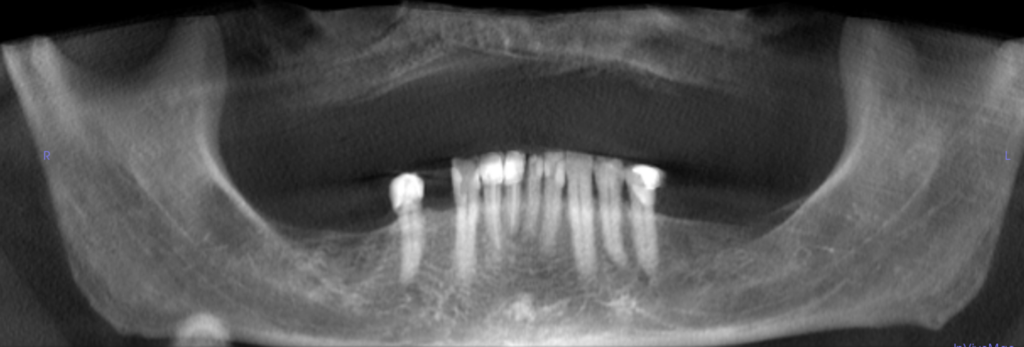

74-year-old man with radiopacity at right mandible

A healthy 74-year-old man presented to his family dentist for an annual recall with no complaints or recent history of trauma. There was an un…